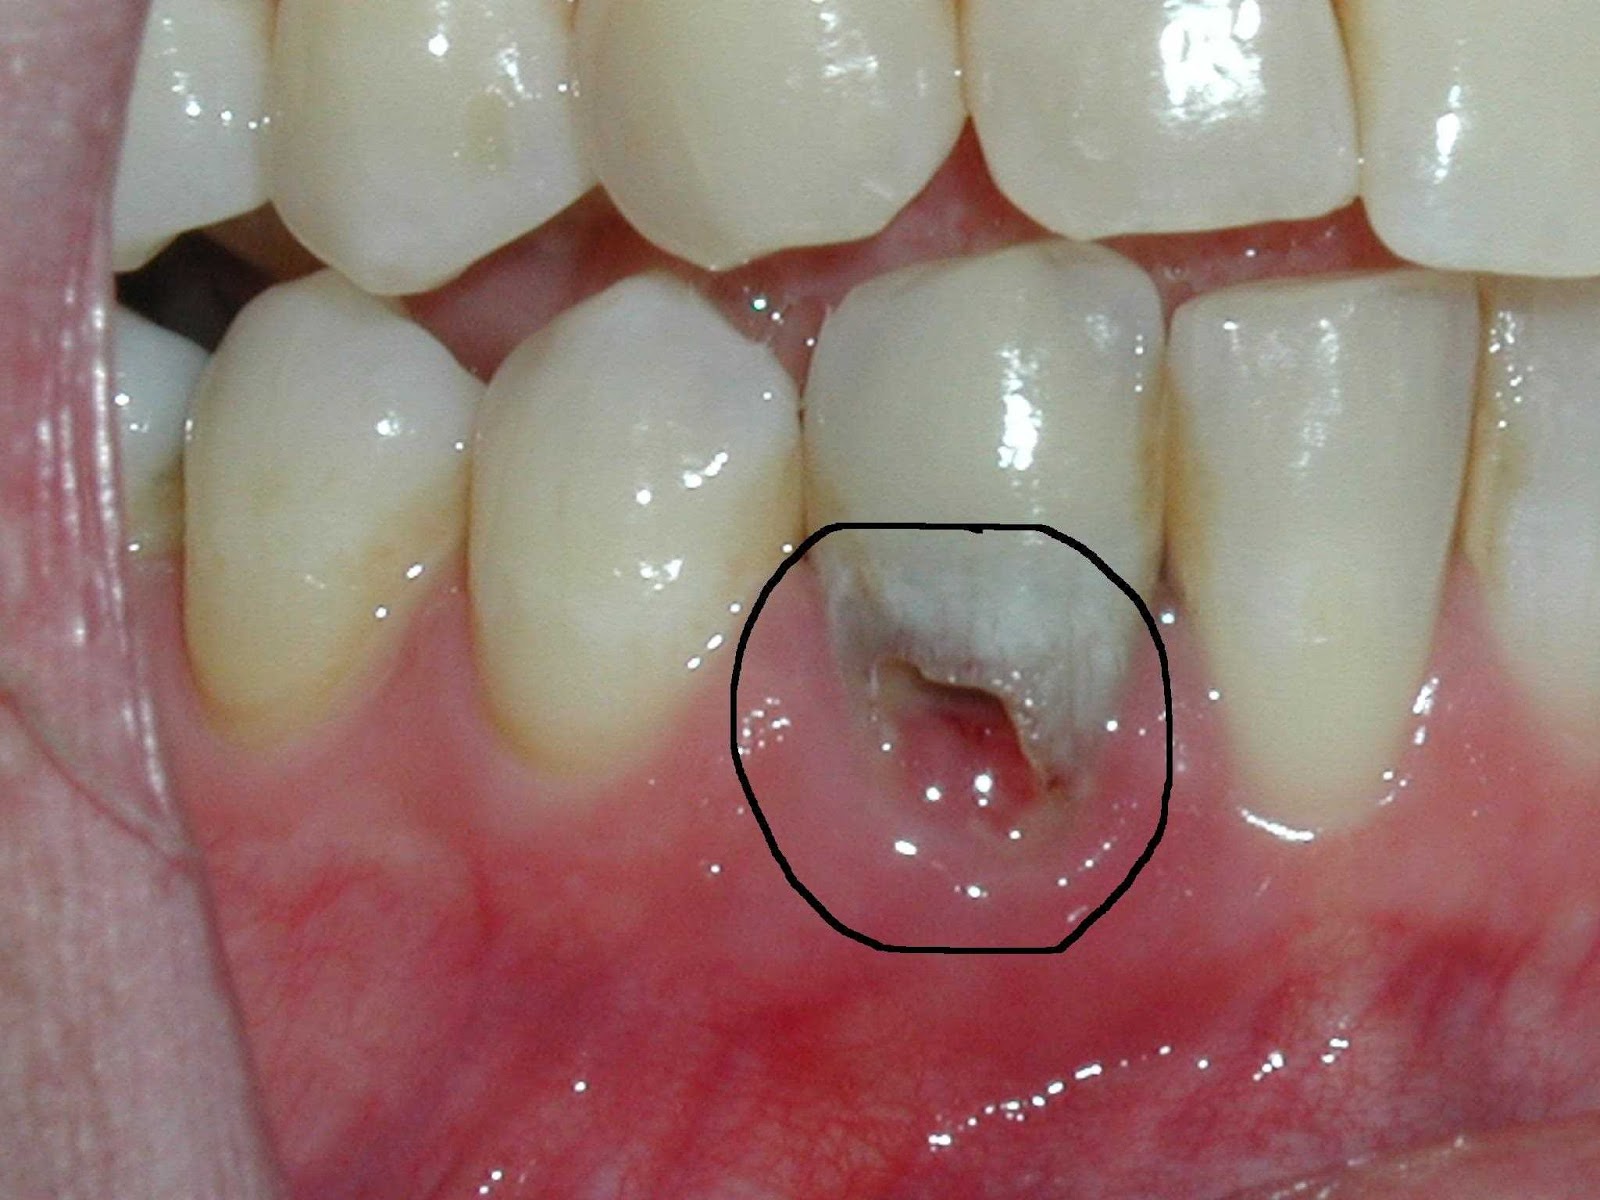

External Root Resorption. What Causes Dental Resorption There are several factors that may lead to resorption of teeth. The most common cause of external. There are several factors that may lead to resorption of teeth. The most common cause of external resorption is. Resorption specifically refers to the. Web tooth resorption is when the tooth structure is damaged or destroyed. Can be caused by trauma to the.. What Causes Dental Resorption.

Internal tooth resorption root canal treatment with 5 canals. What Causes Dental Resorption Web what causes tooth resorption? There are several factors that may lead to resorption of teeth. Web tooth resorption causes. Web tooth resorption is when the tooth structure is damaged or destroyed. The most common cause of external resorption is. Can be caused by trauma to the. Web root resorption is the progressive loss of dentine and cementum through the. What Causes Dental Resorption.

Radiological and Histopathological Features of Internal Tooth What Causes Dental Resorption Web tooth resorption is when the tooth structure is damaged or destroyed. Web root resorption is the progressive loss of dentine and cementum through the continued action of osteoclastic. While resorption of bone is a normal physiological response to stimuli throughout the body, root resorption in permanent. Web tooth resorption causes. Can be caused by trauma to the. There are. What Causes Dental Resorption.